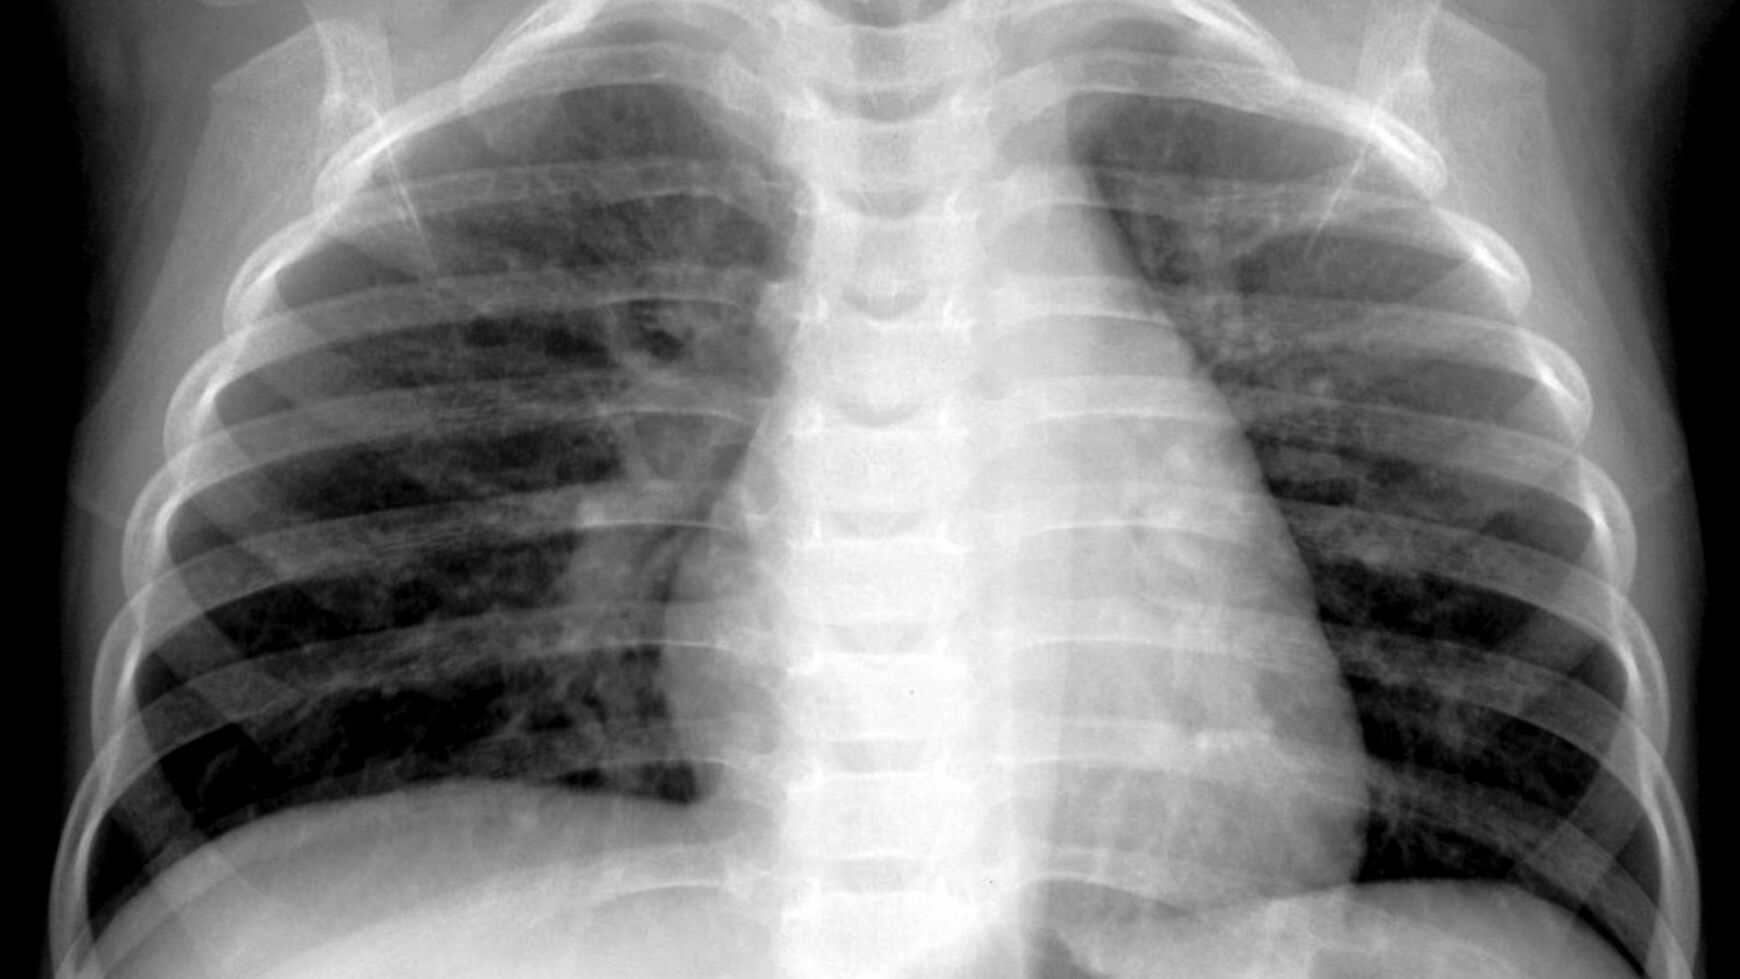

ヒトメタニューモウイルス(hMPV)に感染した生後4カ月の男児のレントゲン(写真:Hilmes et al., Pediatric Radiology, 2017 via The New York Time)